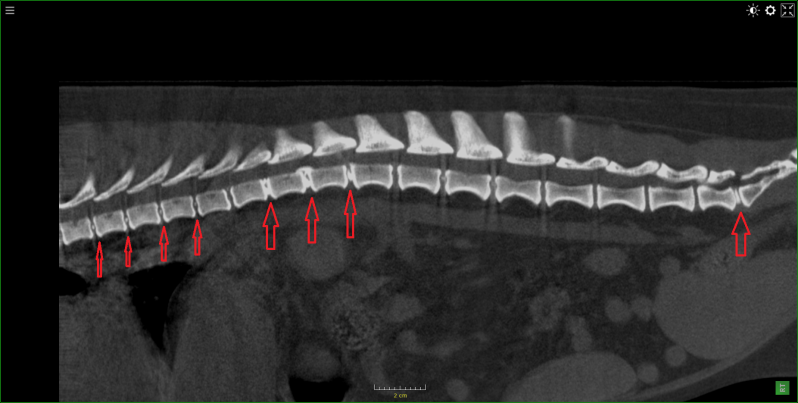

Hond Fila braziliero , van 7 maanden met tandwortel abces .

Gedeelte van het bot rond de tandwortel was aangetast .